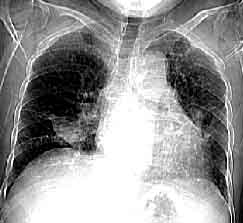

1.檢驗作血白細胞計數及分類。漱口後咳深部痰直接塗片作細菌檢查。應儘量在抗生素套用前作痰、血細菌培養及藥物敏感試驗,培養應反覆多次。作痰培養細菌菌落計數,對於判斷是否是致病菌有一定幫助。疑為軍團菌肺炎者,需作痰或下呼吸道分泌物軍團菌分離,或以直接螢光抗體法,檢測病理標本中的軍團菌,或行血清抗體檢查。2.胸部X線檢查注意陰影特點、部位和範圍。肺炎(鏈)球菌肺炎多呈段或葉大片狀模糊炎性浸潤;金葡菌肺炎系壞死性肺炎,可呈大片絮狀、濃淡不均影,常有一個或多個透亮區,也可為支氣管肺炎表現,血源性者為散在多發膿腫陰影;肺炎克雷伯桿菌肺炎亦呈壞死性表現,上葉多見,呈斑片狀或大葉性,易形成空洞,需與肺結核鑑別,或呈兩側支氣管肺炎改變;軍團菌肺炎早期為單側少量斑片狀實質浸潤,可迅速發展為多肺葉段,下葉多見。